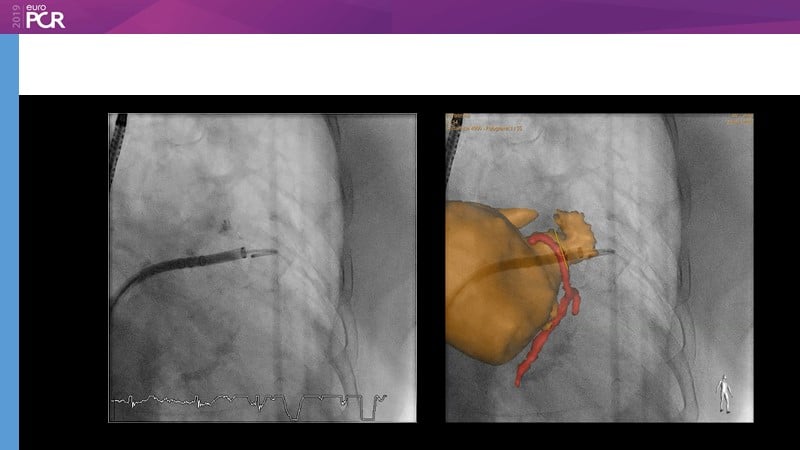

Pre-procedure planning

Previous Next

Optimising procedural outcome and safety